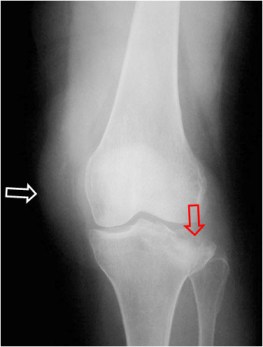

SIGNO FBI

Las iniciales FBI hacen referencia a fat-blood interface, es decir, al nivel líquido-grasa que se ve en radiografías laterales de rodilla (con rayo horizontal) y que corresponde a lipohemartrosis. Indica la existencia de una fractura subyacente, que puede ser visible o estar oculta.

La radiografía anteroposterior de rodilla muestra la fractura del platillo externo de la meseta tibial (flecha roja) y el marcado aumento de partes blandas por el derrame articular (flecha blanca).